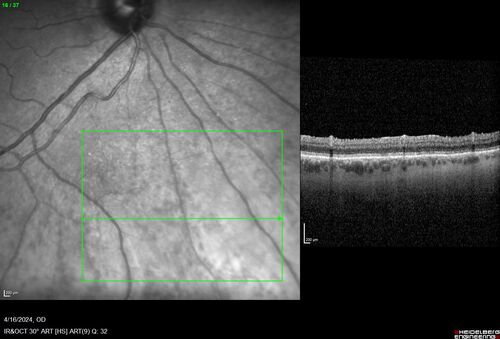

Posterior Pigment Dispersion Syndrome

81 year old man with cataract surgery 30 years ago and normal vision who had bilateral vitrectomy for dense floaters and has pigment on his IOL surface and all over the retina (but not on the cornea) VA 20/25 OU